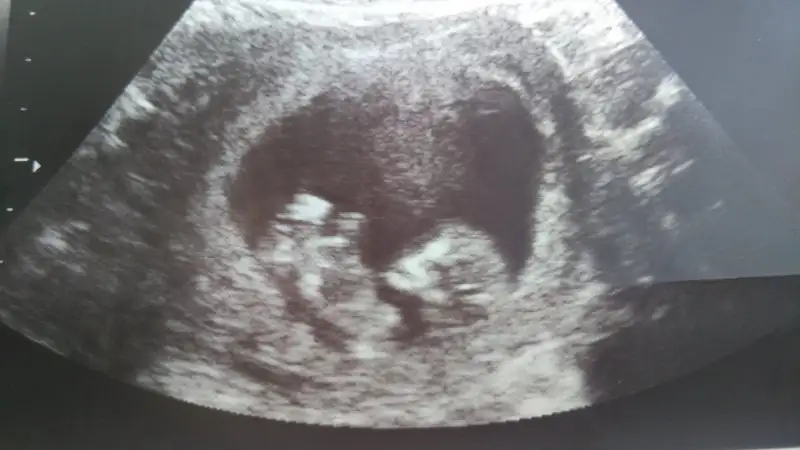

pek gorunmuyo ama benim.icime erkek doğdu gozunaydin canim hayirlisi olsunBunlarda resimlerimiz :) varsa tahminleri alırız